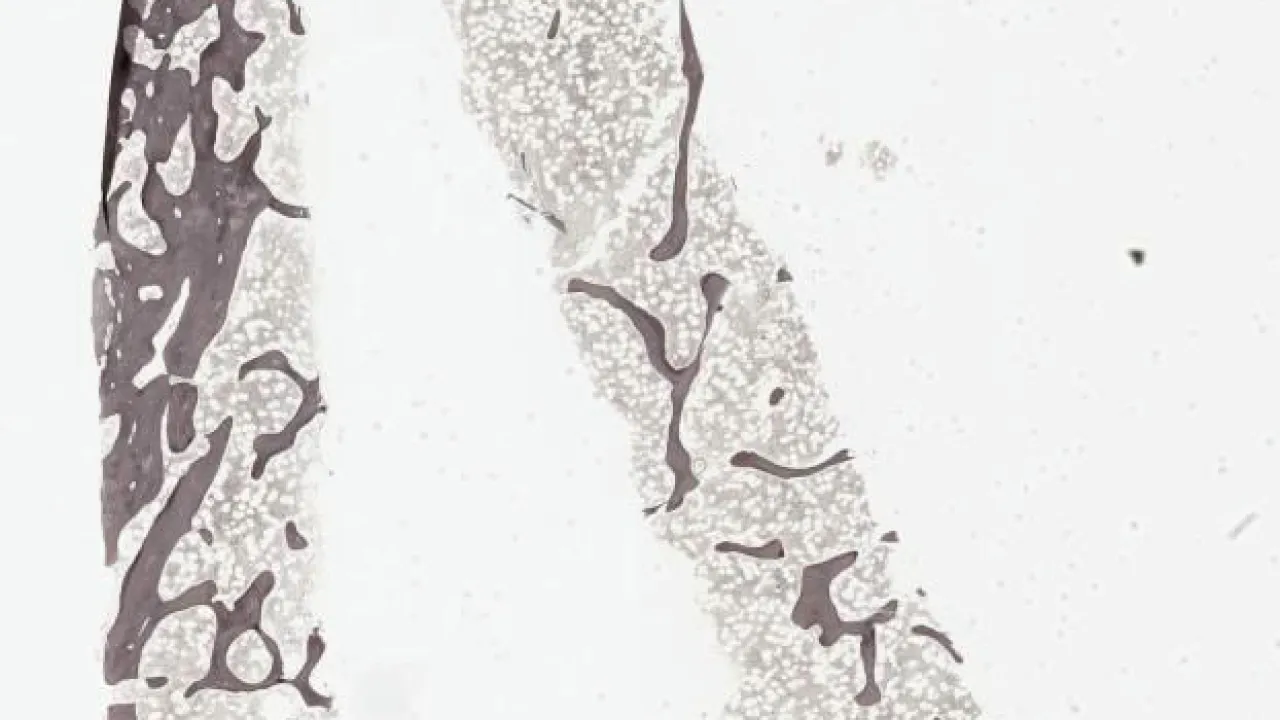

Bone Marrow, systemic mastocytosis, reticulin stain